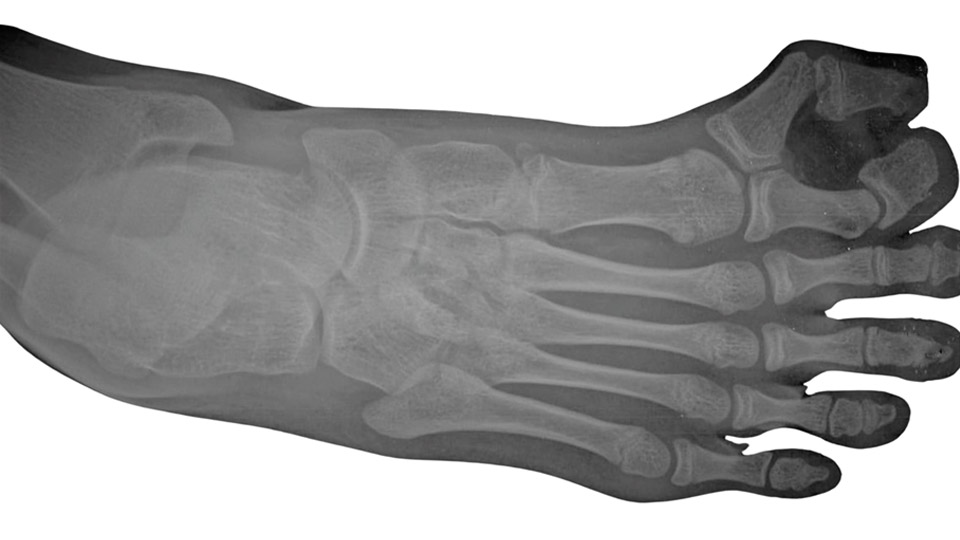

A fizikális vizsgálat során ortopéd szakorvosunk megvizsgálja a láb statikai viszonyait, az ujjak elhelyezkedését, a bőrelváltozásokat, a járáskép esetleges megváltozását. A tapintási vizsgálat során a csontos képletek elmozdíthatóságát, stabilitását és kapcsolódását is értékeljük. A diagnózis megerősítéséhez röntgenfelvétel (RTG) készül a láb elülső és oldalsó nézetéből, szükség esetén kiegészítve ultrahangvizsgálattal vagy MRI-vel, ha az érintett terület ideg- és lágyrészviszonyai részletesebb megítélést igényelnek.